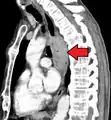

إن أفضل الطرق لتشخيص المرض هي عن طريق التنظير الباطن العلوي حيث يمكن رؤية الورم بشكل مباشر وأخذ خزعات من المناطق المصابة وفحصها مخبرياً، كما يمكن استخدام عدة فحوصات شعاعية للمساعدة في تشخيص المرض وتحديد مدى تغلغل الورم وانتشاره، من أهم تلك التقنيات: التصوير الطبقي المحوري و وجبة الباريوم, وقد يتم إجراء اختبار حركية المريء لاستبيان تضرر عضلات المريء بسبب السرطان.

معرض صور